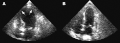

(A) Echocardiogram showing dilatation of the left ventricle in the acute phase (B) Resolution of left ventricular function on repeat echocardiogram six days later

Echocardiogram showing the effects of the disease[56]